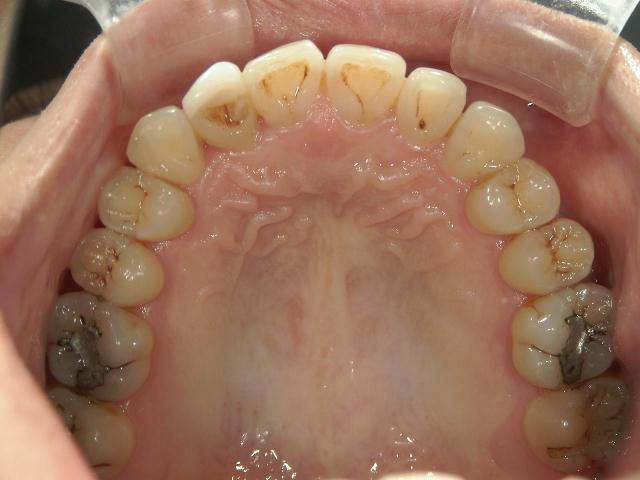

矯正歯科 治療前 上顎